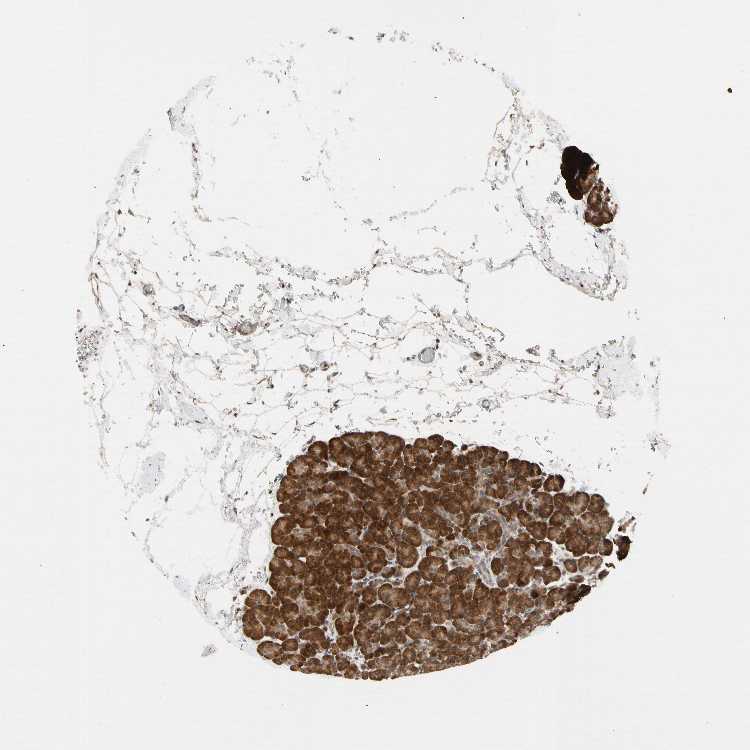

PANCREAS - Antibody stainingi

Antibody staining in the annotated cell types in the current human tissue is reported as not detected, low, medium, or high, based on conventional immunohistochemistry profiling in selected tissues. This score is based on the combination of the staining intensity and fraction of stained cells.

Each image is clickable and will lead to virtual microscopy that enables deeper exploration of all samples and also displays staining intensity scores, fraction scores and subcellular localization as well as patient and tissue information for each sample.

Antibody HPA007191

Exocrine glandular cells High

Pancreatic endocrine cells Medium